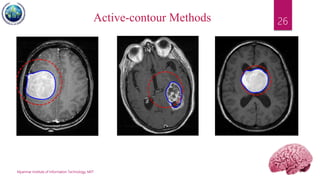

Active-Contour Methods

 Uses of energy forces and constraints for

segregation of the pixels of interest from the

image.

 Snakes: Active contour models. Kass, M.; Witkin,

A.; Terzopoulos, D. International Journal of

Computer Vision 1 (4): 321 (1988).

DOI:10.1007/BF00133570

 A snake is an energy minimizing, deformable

spline influenced by constraint and image forces

that pull it towards object contours and internal

forces that resist deformation.

26Active-contour Methods